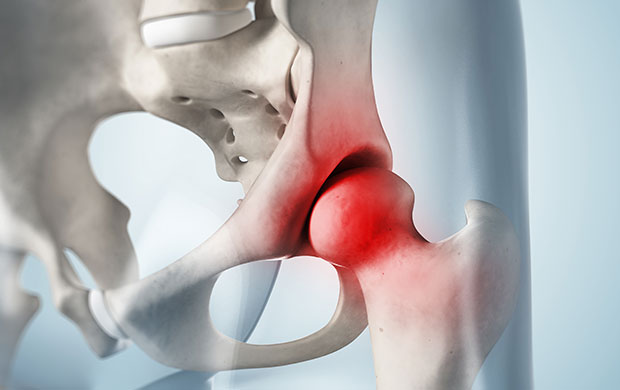

정상적인 대퇴골두가 둥근 탁구공 모양이라면, 무혈성 괴사가 진행된 경우에는 표면이 납작해지거나 형태가 변형되어 보입니다. 뼈에 혈액 공급이 원활하지 않으면 대퇴골두 조직이 괴사하면서 점차 무너져 통증과 보행 장애를 초래합니다. 원인으로는 과다한 음주나 스테로이드 과용 등이 연관된다고 알려져 있으며, 주로 30~50대에서 발병하는 경우가 많습니다. 초기에는 고관절 부위의 통증이 주 증상이며, 병이 진행되면 보행이 어려워지고 다리 길이 차이 같은 변형이 나타날 수 있습니다.

중장년층에서 흔하지만 최근 젊은 환자 비중도 증가하고 있습니다. 엉덩이와 골반 주변의 둔한 통증과 함께 걷는 동안 절뚝거리는 현상이 있다면 대퇴골두 무혈성 괴사나 심한 관절 손상을 의심해 볼 필요가 있습니다. 괴사가 진행되면 골절로 이어져 고관절 기능 손상이 심해질 수 있으며, 원인으로는 과음, 고지혈증, 스테로이드 과다 사용 등이 영향을 줄 수 있습니다.